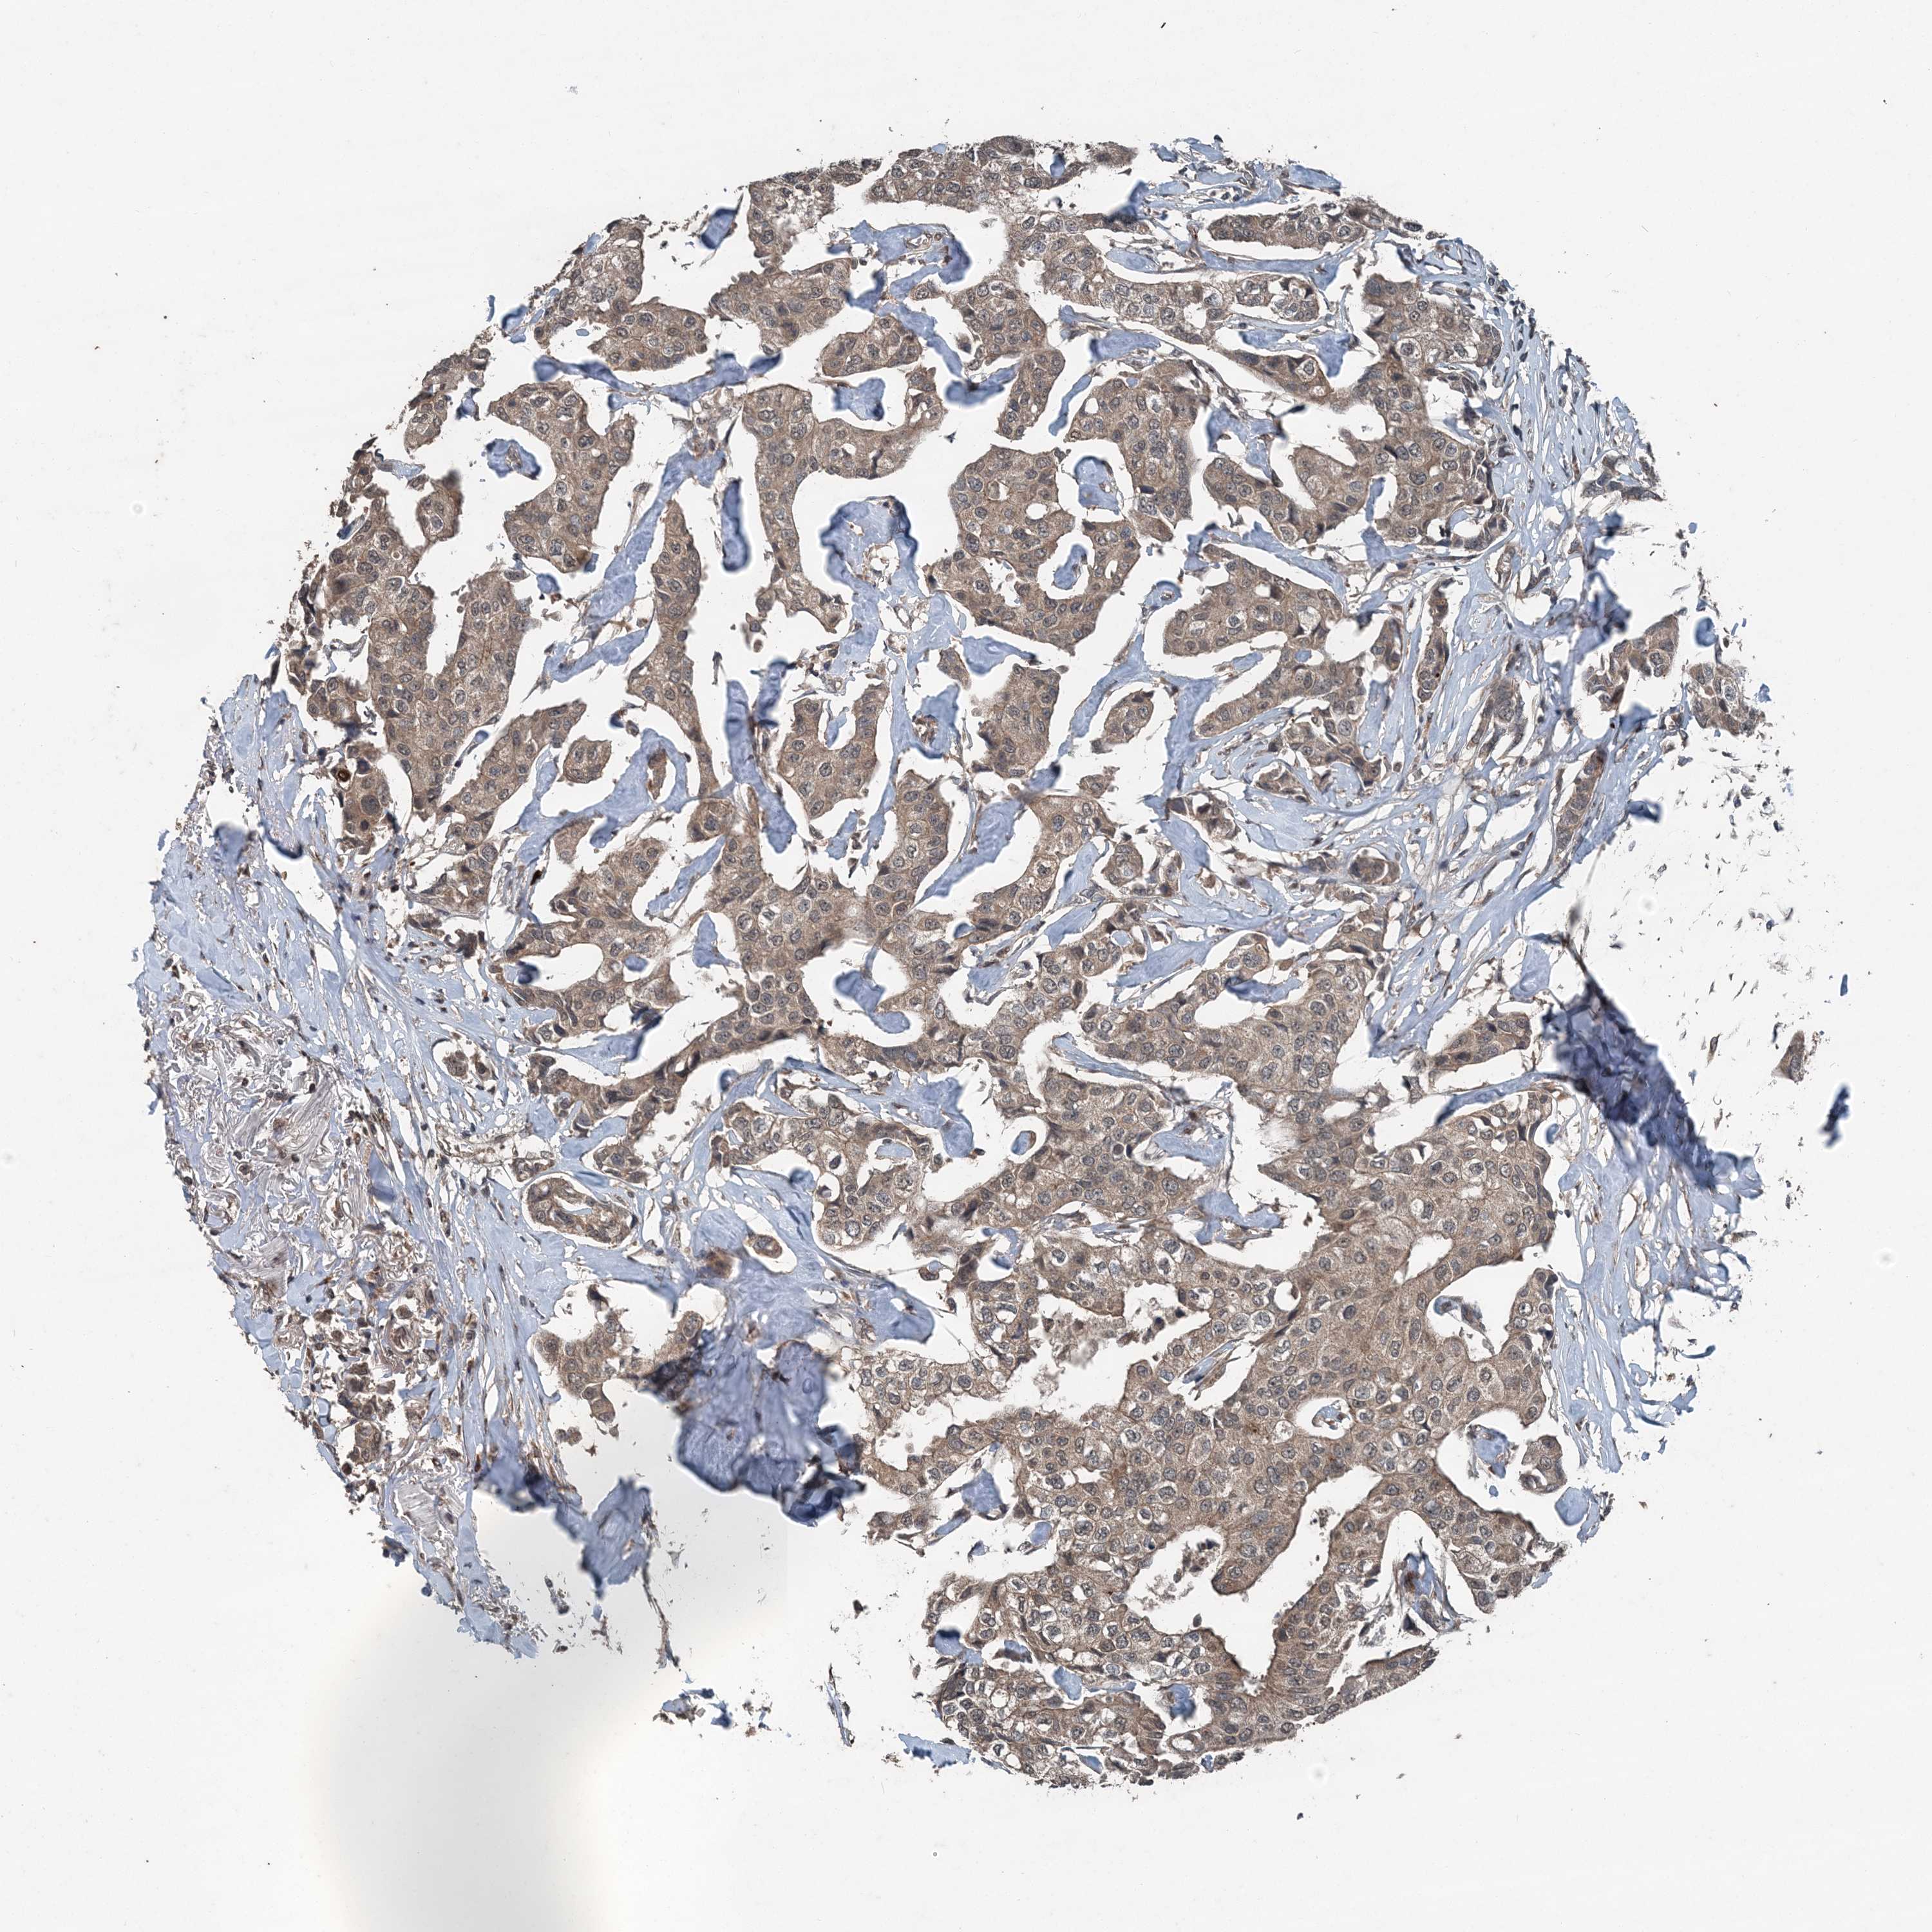

CANCER BREAST CANCER Show tissue menu

BRCA TCGA BRCA VALIDATION PROTEIN EXPRESSION

ANTIBODIES

AND

VALIDATION